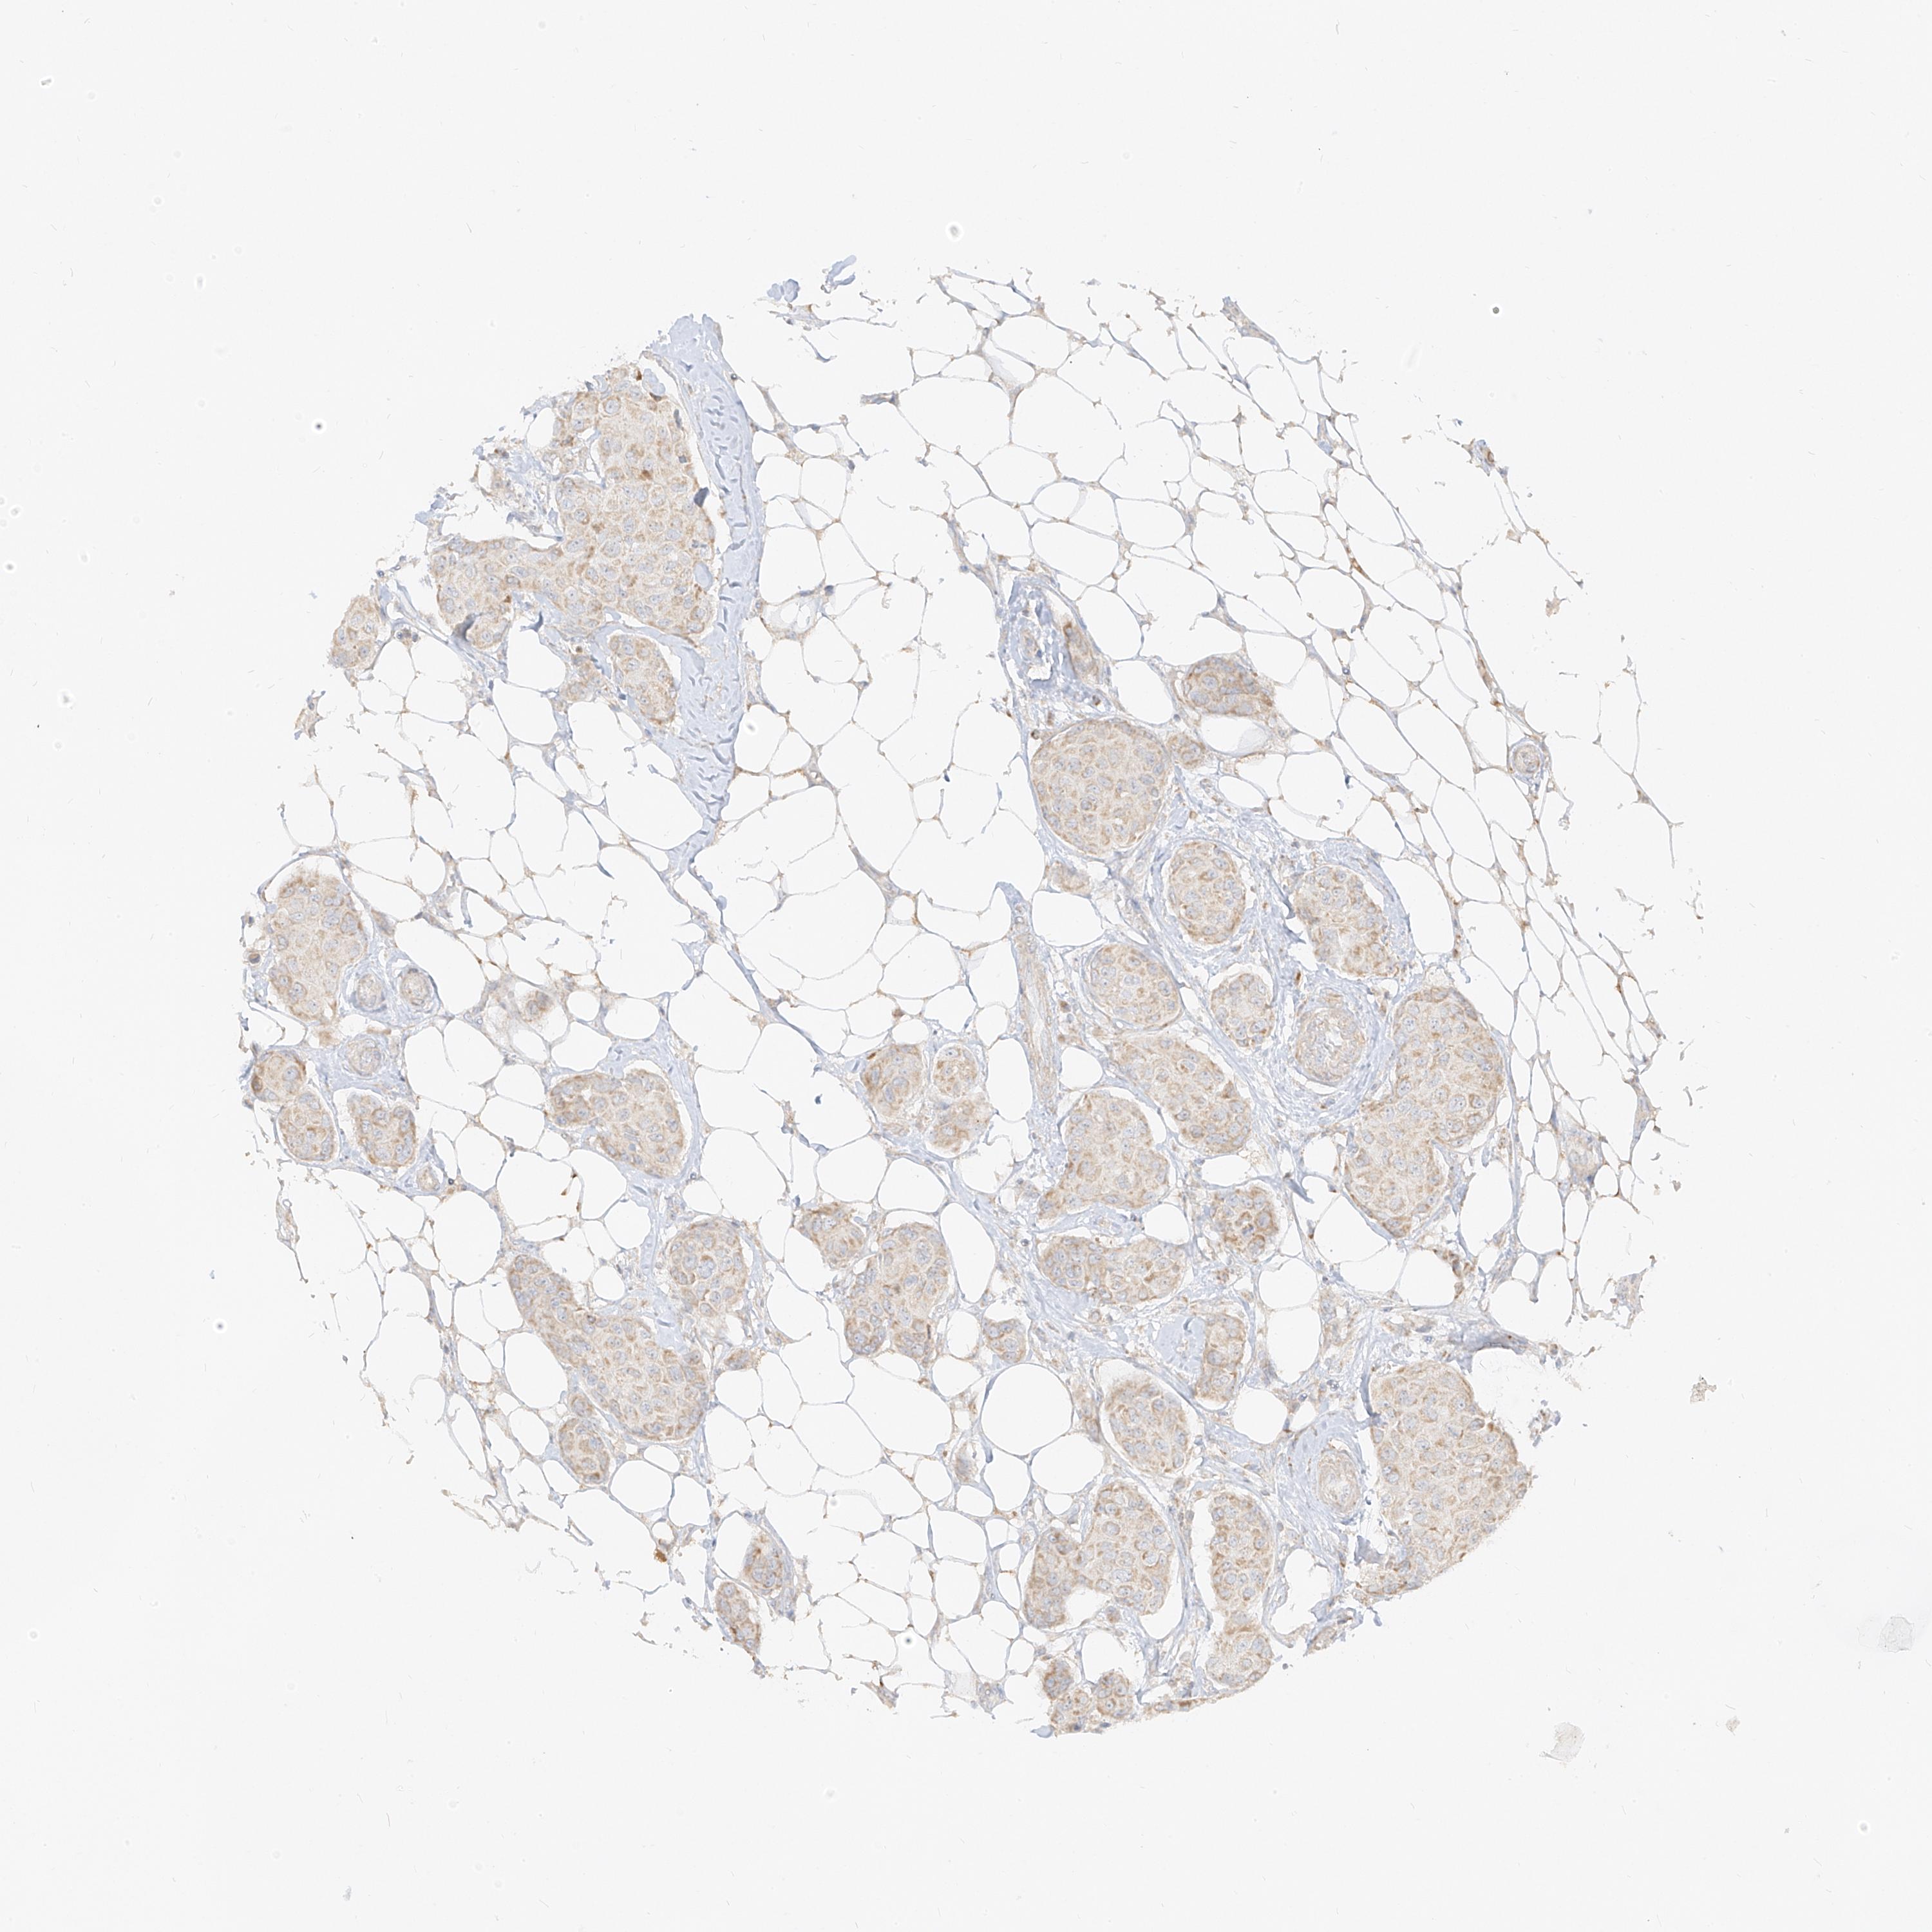

CANCER BREAST CANCER Show tissue menu

BRCA TCGA BRCA VALIDATION PROTEIN EXPRESSION